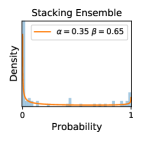

5.1 Distribution of Uncertainty Scores

Distribution of Uncertainty Scores Across Different Severity Levels As explained in Section 3, each uncertainty metric essentially defines an order/ranking among the data points. We conducted an analysis to better understand what data will be assigned high uncertainty under a particular uncertainty metric . Picking out the highest ranked data points (), we calculated the ratio of data points from each SL. Figure 4 summarizes the results as box plots for the Kaggle-DR and the Messidor-2 datasets; additional detailed statistics can be found in Table S.1 in the supplementary materials. From the plot and table, SL1 & SL2 examples account for a higher proportion among the top-ranked uncertain examples across the three ensemble methods. This finding matches our intuition that incipient disease examples (SL1 & SL2) are more likely to be considered uncertain by ensemble methods due to their ambiguity.

Comparing the three ensemble methods in Figure 4, the stacking ensemble method has the highest ratios of SL1 & SL2 data among the high-uncertainty examples it identified under both mean and var. TTA showed slightly better performance than MC-dropout but still falls behind the stacking ensemble method. Considering the fact that SL0 examples accounted for the majority of the dataset, the stacking ensemble method was much more precise (specific) in selecting truly ambiguous data points that were difficult to classify. From Figure 3, we can also see that the stacking ensemble method greatly outperformed the other two methods in finding false negatives under both mean and var uncertainty metrics.

In contrast, the MC-dropout method showed the worst overall performance among the three, as it can be seen from the high ratios of SL0 examples among the uncertain negatives in Figure 4. The histograms in Figure 2 provides another perspective to look into the phenomenon, where a decent proportion of MC-dropout model’s predictions on SL0 inputs entailed low confidence (far from 0 or 1), which from another angle explained why MC-dropout was less specific in terms of lower FNP; many no-DR inputs (i.e. SL0) were erroneously assigned high uncertainty by MC-dropout models.

It is still an open question why the evaluated MC-dropout networks signaled relatively high uncertainty on SL0 & SL3 & SL4 data that are less likely to be ambiguous. We conjecture that much of the “uncertainty” indicated by disagreement among test-time dropout samples actually reflects the stochastic nature of dropout networks rather than the real decision uncertainty associated with the data. It is worth noting that the MC-dropout model we evaluated was not weak per se; they all achieved above Area Under Curve (AUC) scores on test sets. The weakness of individual test-time samples (which explains their low-confidence predictions on SL0 & SL3 & SL4) might have been hidden when they are aggregated into an ensemble—a well-known advantage of ensemble learning. Our results suggested that the uncertainty information given by implicit ensemble methods such as MC-dropout and TTA might not be as reliable as that from explicit ensemble approaches (e.g., stacking ensembles). Similar findings on MC-dropout can be found in some previous papers [1].

As discussed in Section 5.1 and Section 5.3 in the main paper, the mean metric and the stacking ensemble will have better performance in the precision (specificity) on the ambiguous data. Here, more detailed results are shown in Figures S.3 & S.6 and Table S.1. Figures S.3 & S.4 show the histograms of the uncertainty score for Kaggle-DR and Messidor-2 datasets that are the in-distribution (i.d.) dataset in our experiment and FigureS.5 & S.6 show the histograms for ImageNet and CIFAR-10 datasets, which is the o.o.d. datasets in our experiment. Each group of histograms contains results from the three evaluated ensemble methods (stacking ensemble, MC-dropout and TTA) and the three uncertainty metrics (mean, var and kl). Additional detailed results not displayed in Figure 4 can be found in Table S.1, which shows the proportion of the data of different SLs varies across different . For comparison, we also included in Table S.1 the results from single learners, and the proportions of data of different SLs (before any selection was made).